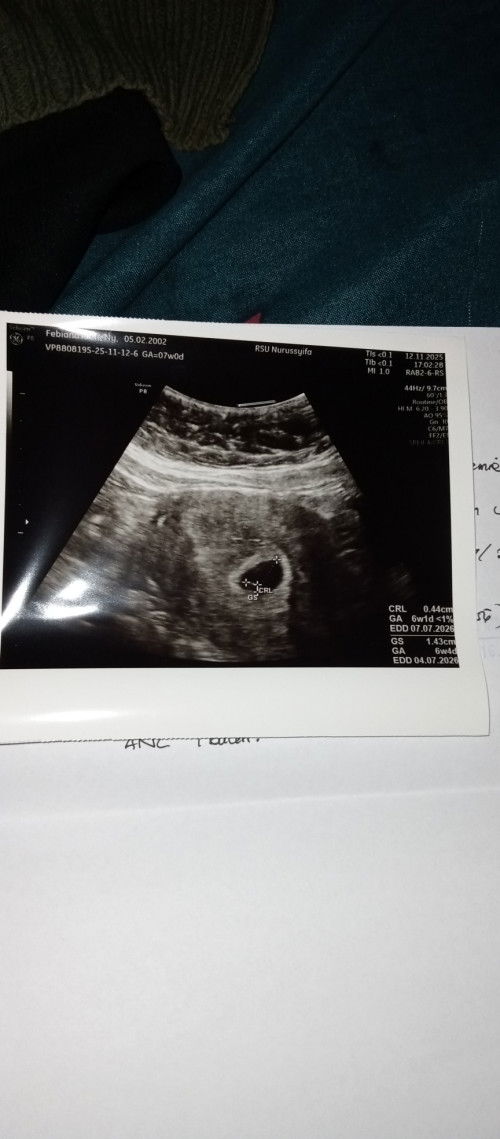

Iya Bun, makanya saya ovt. Mudah-mudahan nanti pas USG ulang ada ddx bayinya.

sama aku jg minggu kmrn usg kata nya baru kantung

saya ada janin nya bun tpi bru 1 cm an kcill bngt ps usg keliatan kedip"kcill ..tpi ps dicetak ga keliatan